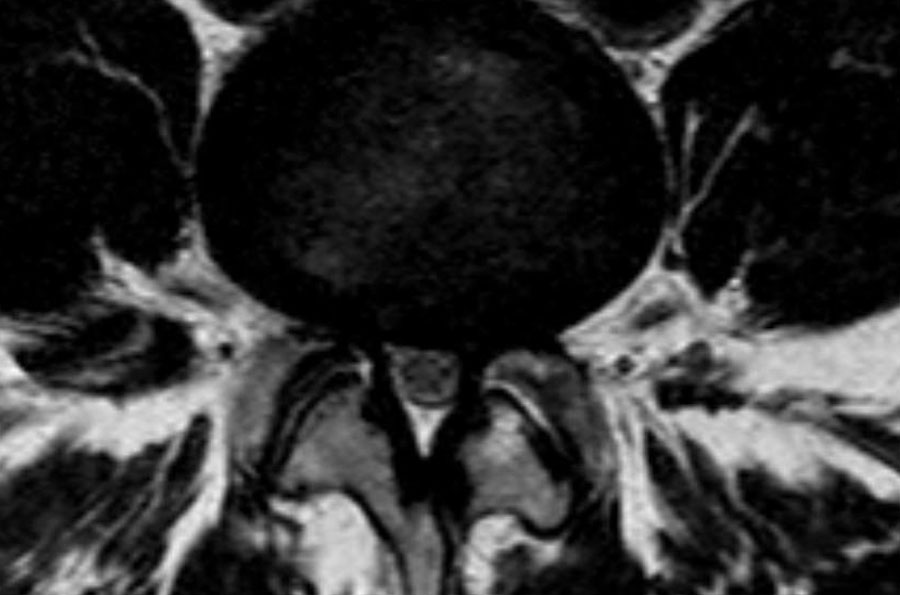

Cuộn qua các hình ảnh để quan sát đường đi của các rễ thần kinh tại mức độ đĩa đệm, ngách bên, lỗ liên hợp và ngoài lỗ liên hợp.

Tại mỗi mức độ có thể thấy các bệnh lý đặc trưng, nhưng có sự chồng lấp đáng kể.

Ví dụ, đĩa đệm có thể thoát vị và gây chèn ép thần kinh tại mức độ đĩa đệm, nhưng cũng có thể di trú xuống tầng thấp hơn và chèn ép rễ thần kinh trong ngách bên, hoặc di chuyển lên trên và gây chèn ép tại mức độ lỗ liên hợp hay ngoài lỗ liên hợp.

Các dấu hiệu tại các mức 1-4 như sau:

- Tại mức đĩa đệm, có hẹp ống sống tối thiểu do phình đĩa đệm và thoái hóa khớp mỏm khớp.